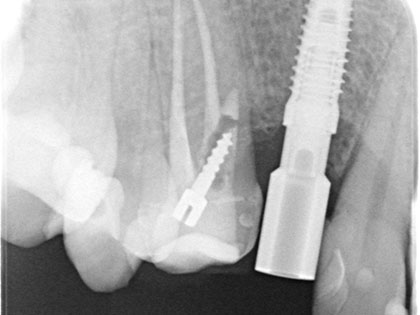

インプラント 症例紹介

インプラント症例

右下奥歯にインプラント治療を行った症例

右下奥歯が腫れて噛むと痛いとの事で来院され、インプラント治療を希望された患者様の症例になります